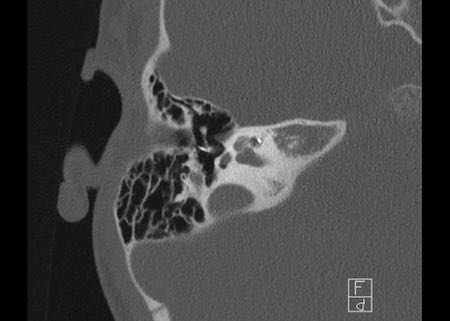

Bên trái là hình ảnh của một bé gái 2 tuổi.

Các hình ảnh từ kết quả chụp CT được thực hiện trước khi cấy ốc tai điện tử.

Quan sát thấy dị dạng nhẹ ở đỉnh ốc tai – không có sự phân tách giữa vòng thứ hai và vòng thứ ba, và trụ ốc tai xương vắng mặt.

Cống tiền đình bình thường.